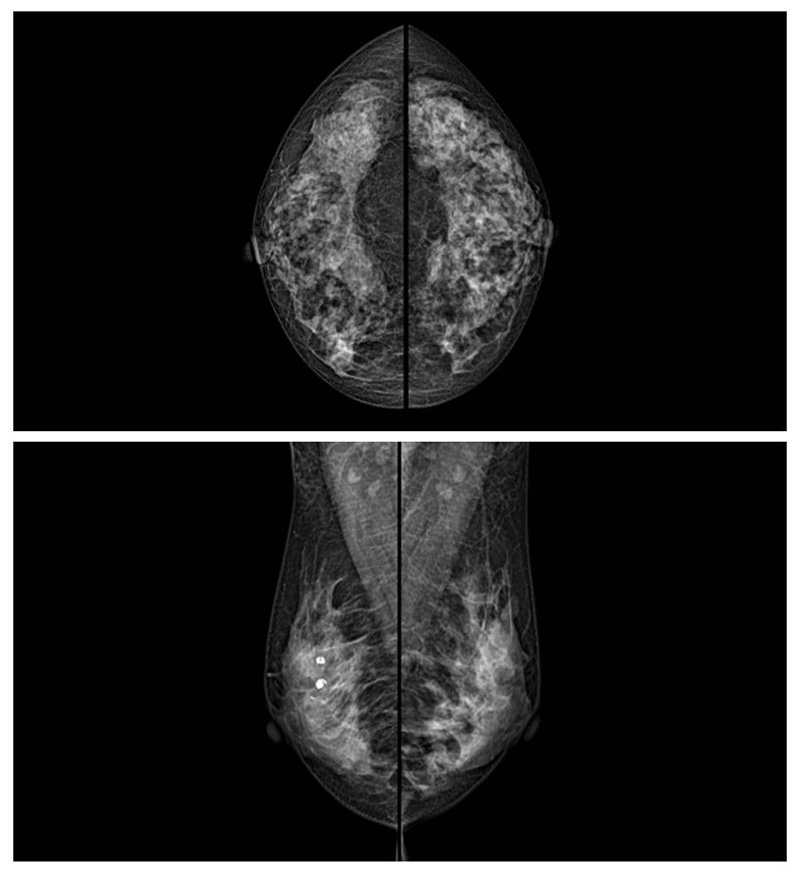

乳腺癌的發(fā)生率越來越高,已經(jīng)是我們國家的癌癥之一已成為女性健康“頭號殺手”。乳腺DR可提高乳腺癌早期檢出率并精準定位。發(fā)現(xiàn)和診斷早期乳腺癌最有效的方法之一,明顯利大于弊女性都要重視乳腺的檢查。輻射很小最簡便、最可靠、無創(chuàng)性檢查手段,做一次乳腺DR的劑量相當于7周的正常生活。尤其是對于40歲以上的女性尤為重要,那么乳腺DR是怎么進行檢查的呢?我們來了解一下,為廣大朋友在檢查前有點心理準備。檢查時候是避開經(jīng)期的前后,月經(jīng)來后的7天左右比較合適。需要脫衣服檢查,根據(jù)拍片的擺位要求,有頭尾位置,內(nèi)外斜位,還有側(cè)位。定點放大壓迫方法可以更細微清晰的檢查出病灶。